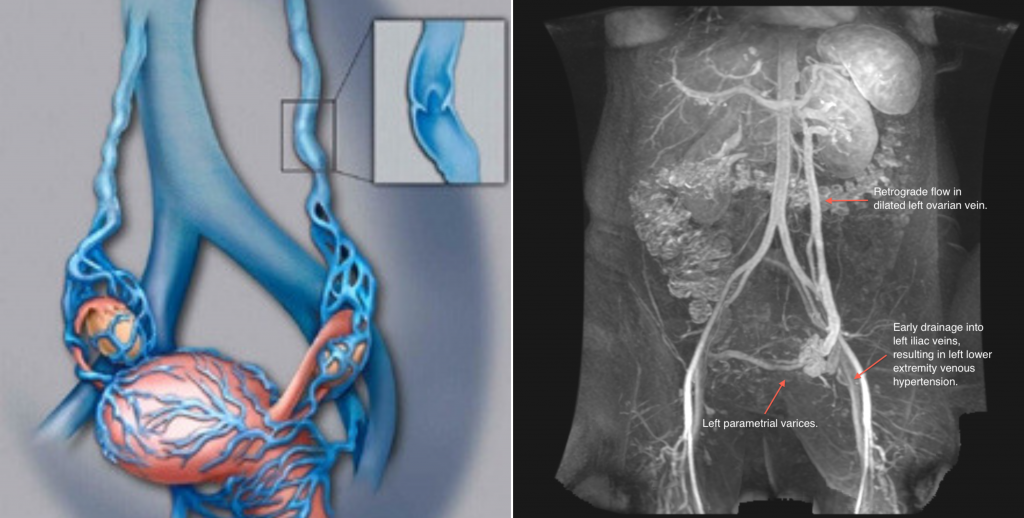

Bicara varises pelvis pada wanita, maka tidak bisa dilepaskan dari masalah kegagalan dalam aliran darah. Akibatnya, vena ovarium mengalami kehilangan integritas dan elastisitas pada katup. Lalu dinding pembuluh darah membentang, rongga vena pun mengembang.

Throughput-nya hilang, dan vena tidak bisa lagi menyusut dengan benar. Pada awal perkembangan penyakit ini, wanita mulai merasakan sakit.